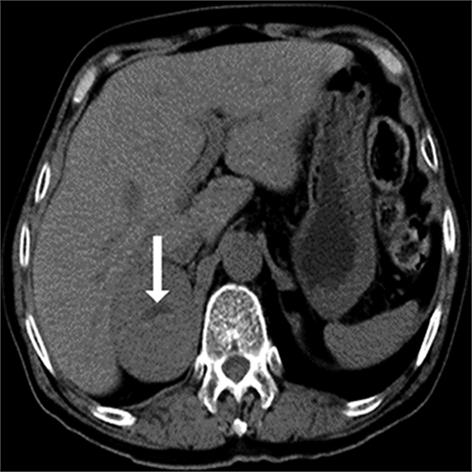

• 嗜铬细胞瘤及副神经节瘤不同生化表型的CT征象对比研究

2024, 49(2):203-209. DOI: 10.13406/j.cnki.cyxb.003433

摘要 (51) HTML (33) PDF 3.10 M (96) 评论 (0) 收藏

摘要:目的 分析生化阴性嗜铬细胞瘤及副神经节瘤(pheochromocytomas and paragangliomas,PPGLs)的电子计算机断层扫描(computed tomography,CT)征象是否有别于生化阳性PPGLs,同时了解生化阳性PPGLs不同表型的CT征象是否存在差异。方法 回顾性分析131例PPGLs患者的术前腹部增强CT图像,包括肿瘤位置、大小、形态、囊变坏死、液-液分层、钙化、向心结节状强化、肿瘤内粗大血管、强化包膜、绝对廓清率及相对廓清率。根据生化水平,将患者分为生化阳性组和阴性组,阳性组进一步分为去甲肾上腺素型、肾上腺素型及多巴胺型。比较各组及各表型间的CT征象差异。结果 相较于生化阴性组,阳性组PPGLs更大(Z=-2.064,P=0.039)、囊变坏死(χ2=6.610,P=0.010)及向心结节状强化(χ2=3.909,P=0.048)的比例更高;相较于去甲肾上腺素型,肾上腺素型PPGLs更大(Z=-2.036,P=0.042)、强化包膜比例更高(χ2=7.242,P=0.007)。结论 肿瘤大小、囊变坏死及向心结节状强化的CT征象有助于术前诊断生化阴性PPGLs,肿瘤大小及强化包膜有助于解释去甲肾上腺素型及肾上腺素型PPGLs不同临床表现产生的机制。